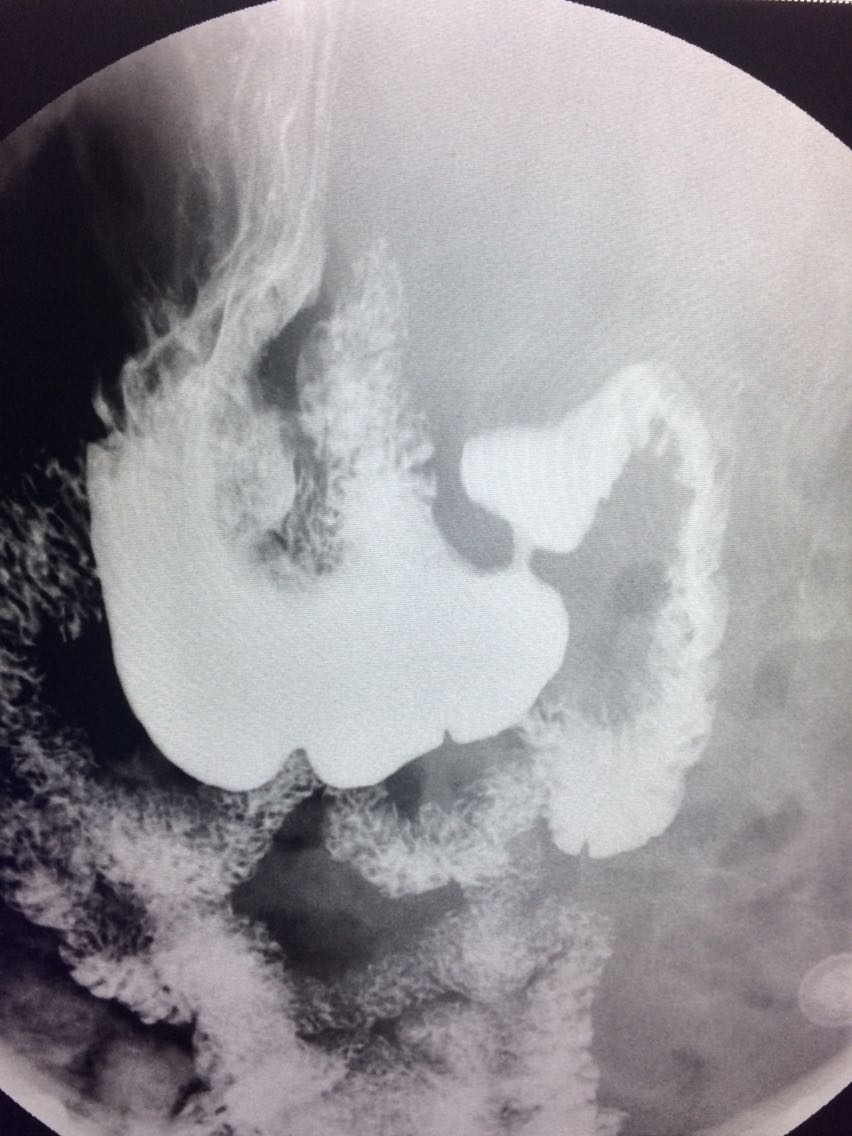

一例溃疡型胃癌。

男,45岁 反复胃疼5年余。 5年来,反复出现胃疼,进食后半小时加重,经常感觉饥饿,当地按胃溃疡,给予阿莫西林,奥美拉唑治疗,具体不详,效果欠佳,遂入院,入院来,饮食睡眠,二便可。 既往体健。 入院上消化道造影如图。

讨论,诊断及鉴别诊断? 胃溃疡的影像表现? 溃疡良恶性的鉴别? 入院后行胃大部切除术。 诊断,胃腺癌。